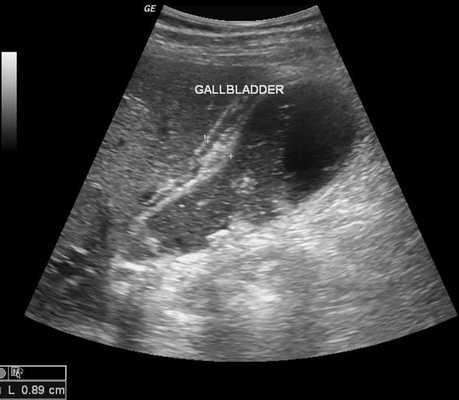

1. Субкостальный доступ (рис. 2, а). Положение датчика косое ниже реберной дуги, параллельно ей. Желчный пузырь проецируется чаще всего по среднеключичной линии. При правильном расположении датчика желчный пузырь на этом срезе утоплен в паренхиму печени. Осуществляя наклоны датчика в направлении ближе к позвоночнику или ближе к реберной дуге, можно увидеть долевые ветви воротной вены (правую и левую) и нижнюю полую вену (см. рис. 2, а); это дополнительные ориентиры для поиска желчного пузыря [6].

Рис. 2. Желчный пузырь: субкостальный доступ (а; по [5]); интеркостальный доступ (б) и биометрия (в; по [5]).

2. Интеркостальный доступ. Датчик расположен параллельно ребрам в межреберье, ориентировочно кнаружи от среднеключичной линии. При этом положении датчика (рис. 2, б) в основном видна правая доля печени, желчный пузырь виден снизу печени, прилежит к ней, примыкает к углу края печени. Дополнительные ориентиры — ствол воротной вены, который в глубине печени разделен на правую и левую долевую ветви, и латерально справа — нижняя полая вена.

Биометрические параметры желчного пузыря и желчных путей. Размеры желчного пузыря очень вариабельны (у пациентов разных конституциональных типов, в зависимости от наполнений, особенностей гладкой мускулатуры, того, как она реагирует на сокращение).

Стенку желчного пузыря следует измерять на том участке, который находится ближе к датчику, так как эффект дорзального усиления приводит к тому, что может быть впечатление большей толщины. Если это интеркостальный доступ (рис. 2, в), то должна быть измерена дорсальная (передняя) стенка желчного пузыря — примыкает к висцеральной поверхности печени, а не вентральная (задняя).